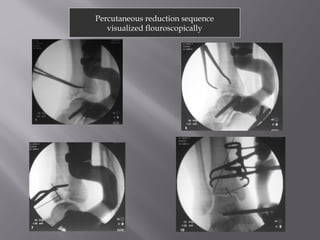

Percutaneous reduction sequence

visualized flouroscopically

Percutaneous reduction sequence visualized flouroscopically